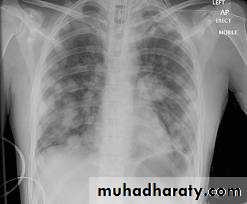

Common radiological presentations of bronchial carcinoma

*Unilateral hilar enlargement*Peripheral pulmonary opacity

*Lung, lobe or segmental collapse *Pleural effusion

*Broadening of mediastinum, enlarged cardiac *shadow, elevation of a hemidiaphragm

*Rib destruction